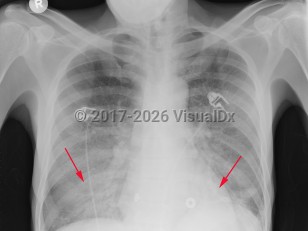

Pneumocystis jirovecii pneumonia

Typical onset in patients with HIV is insidious with a fever, dry cough, and progressive shortness of breath with exertion. There may be associated chest pain. Hemoptysis is not typical. Symptoms may progress for weeks or months before patients seek medical care.

The symptoms are typically more acute in onset and more severe in non-HIV-infected patients. These patients may present with respiratory failure.

Physical examination usually reveals fever, tachycardia, and tachypnea. Breath sounds are often normal, but in up to one-third of adults, rales are present. Impaired oxygenation is a common finding, particularly with ambulation, with varying degrees of hypoxemia and elevated alveolar-arterial (A-a) oxygen gradient.